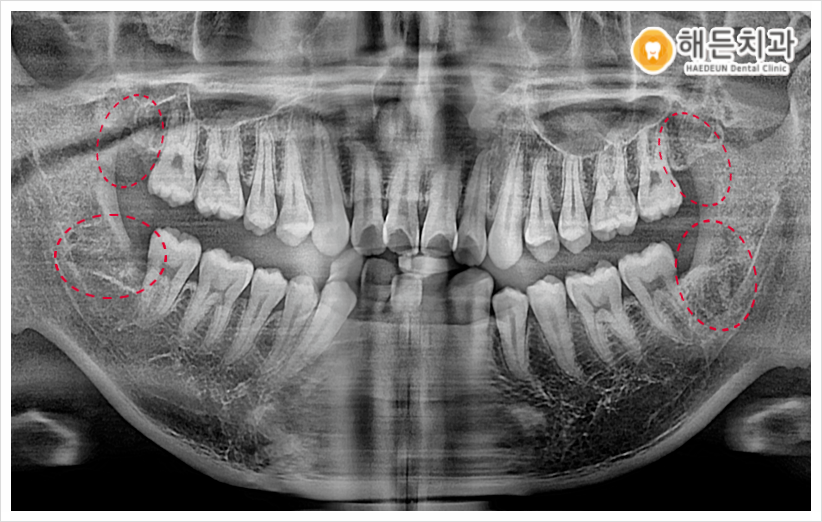

오늘 소개해 드릴 분께서는 오른쪽 아래 사랑니 주변이 불편하다며 본원을 찾아주셨는데요. 평소 음식물도 잘 끼고 잇몸이 부었다 가라앉았다 반복해 왔다고 말씀해 주셨습니다.

파노라마 사진을 촬영하여 확인해 보았더니 사랑니가 위아래 모두 맹출이 되어있었으며, 오른쪽 아래를 제외한 나머지 3개는 비교적 올바른 방향으로 맹출이 되어있었는데요.

하지만 위치적 특성상 맨 안쪽에 위치해 있다 보니, 칫솔질의 접근이 어려워 위생관리가 잘되지 않는 상태였습니다.

이 경우 계속 방치하게 되면 차후 충치가 생기거나 주변 치아에도 영향을 끼칠 수가 있기 때문에, 위생적인 구강 관리를 위해서는 발치하는 것이 좋다고 판단이 되어 환.자분과 꼼꼼한 상.담을 진행한 후에 사랑니 4개를 모두 발치하기로 계획하였습니다.

그리고 파노라마 사진상에서 아래턱 하방으로 지나가는 하치조 신경과 사랑니가 인접해 있는 것을 확인할 수 있었는데요.

발치 시 하치조 신경을 건들게 되면 신경 손상의 위험이 있어 일시적 혹은 영구적으로 감각 이상을 초래할 수 있고, 근육 움직임이 이상해지는 등 부작용이 생길 수 있기 때문에 발치 시 주의가 필요한 케이스였습니다.